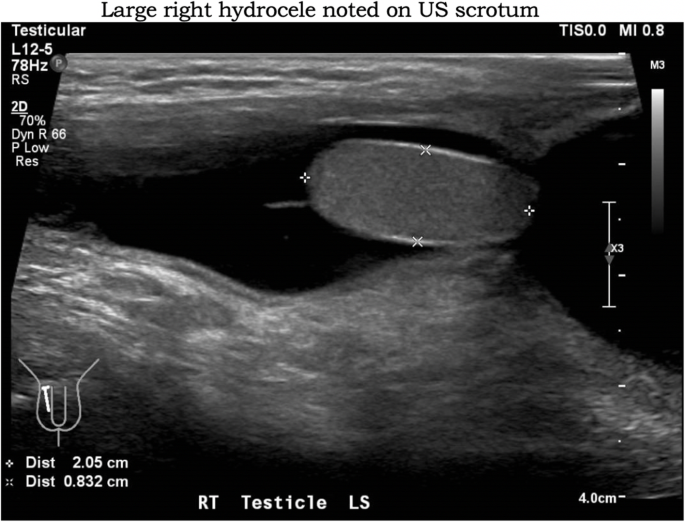

He developed a sudden onset of right scrotal swelling on day 8 of fever. Ultrasound scrotum performed showed a large right hydrocele (Fig. 1) and a small right testis appendix, with no focal abnormalities noted in left testis or the epididymis. The right hydrocele extended into the inguinal region, in-keeping with a patent processus vaginalis. No whirlpool sign was seen bilaterally. The Paediatric Surgeon opted to manage the child conservatively, as there was no clinical or sonographic evidence of epididymal torsion or infection.